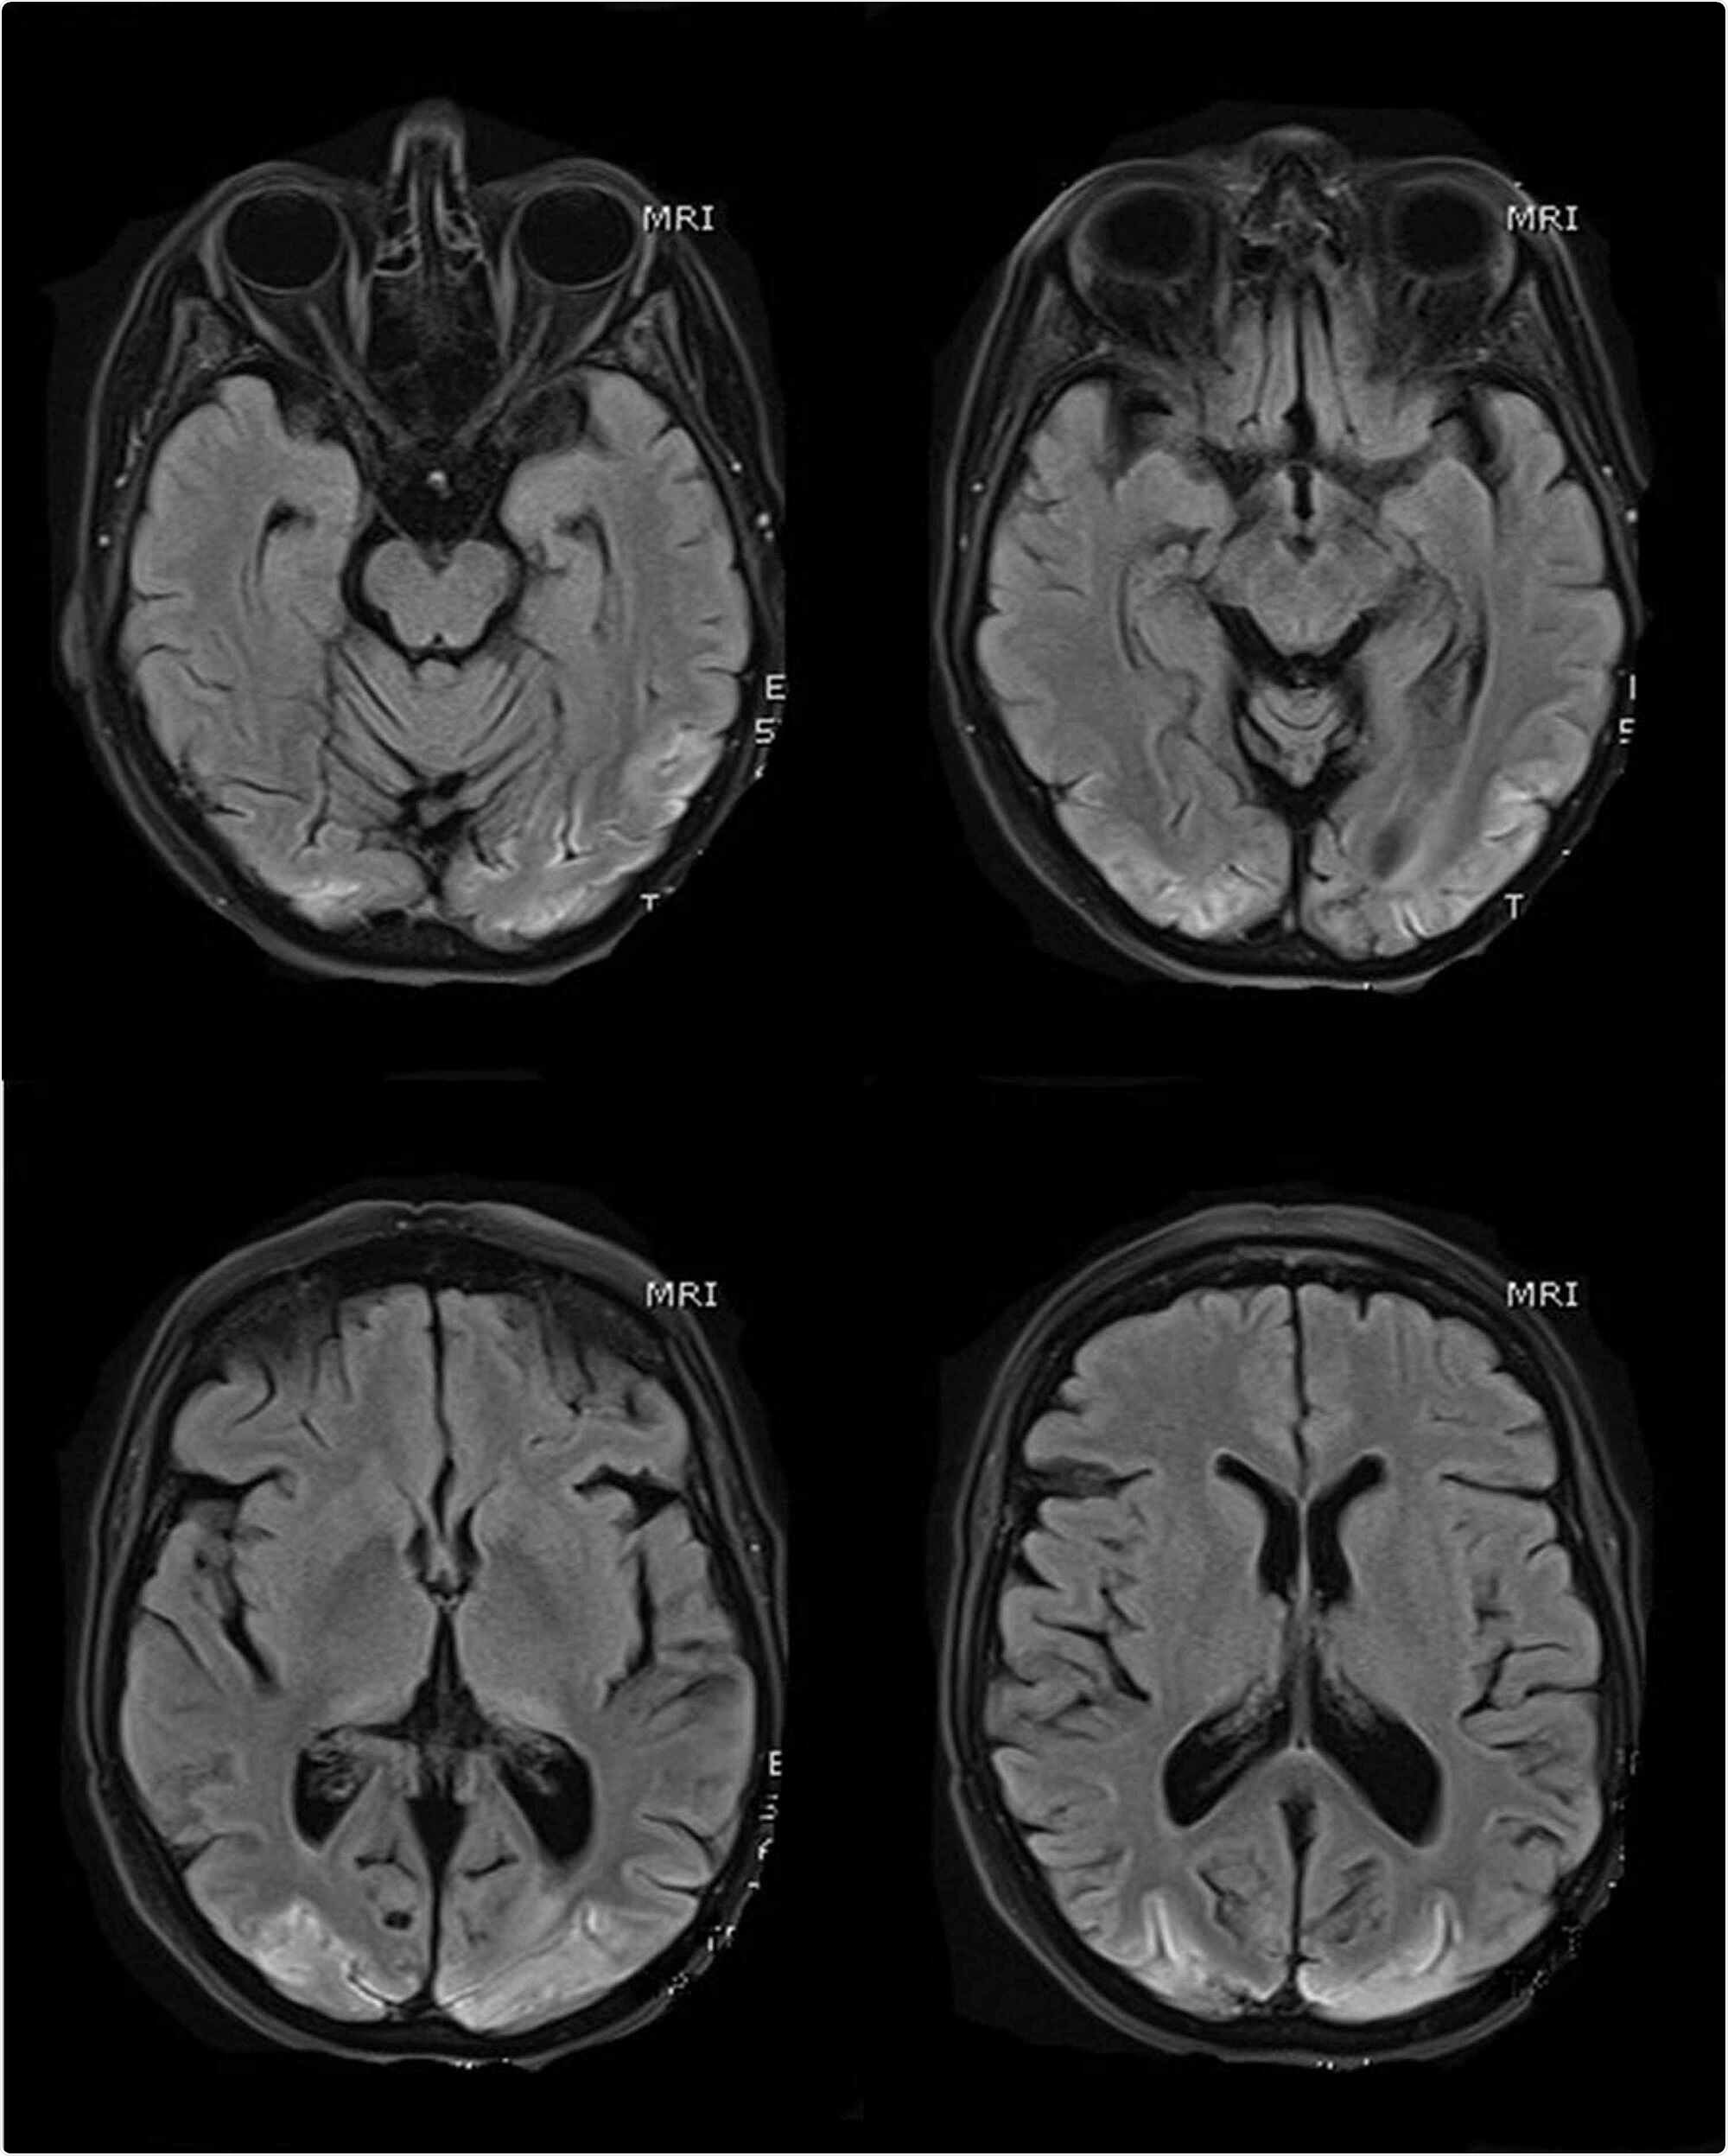

MR scans of the brain (selected T1 sequences) show bilateral symmetrical hyper-intensity involving the bilateral occipital lobe cortex; the changes are consistent with cortical pseudo-laminar necrosis as a complication of posterior reversible encephalopathy syndrome (PRES)